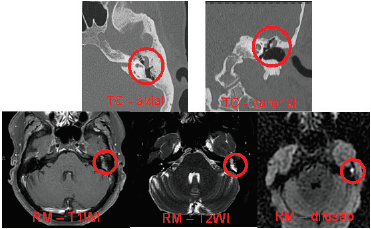

Paciente do sexo feminino, 63 anos, queixa-se de zumbido no ouvido esquerdo. Foram realizados estudos de ressonância magnética e tomografia computadorizada, cujos principais achados seguem abaixo:

Assinale a alternativa que aponta o diagnóstico mais provável para o caso.